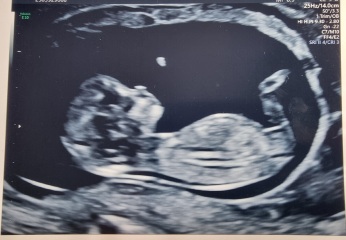

Hiya ladies, I'm new to mums net. I'm 13 weeks 4 days and I done the nub theory last week on gender experts. They done it based on the skull. I have no clue about it all really.. I just saw it as a bit of fun. Can anyone tell me what you think from my scan please? Thank you 😘

Nub theory prediction wrong?

@Jamiexx boy x

@Jamiexx id go with boy!

Thank you! The gender experts said girl by the skull, but from what pictures I have looked at of the nub theory then it looks like a boy to me too! I've been thinking it's a boy anyway. I'll have a very happy son if it's a boy! this baby was a massive surprise I have only 1 child a 15 year old. I always really wanted more but I had loads of complications for10 years in my belly following a serious car accident so having another baby had never been the right time, I just made peace with only having one and surprise! So it really doesn't matter to me if it's a boy or a girl as long as it's ok and I think my son will melt either way 🤣 xxx